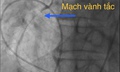

Lão nông ngã giữa đồng, suýt chết vì nhồi máu cơ tim

Y tế - 09/10/2025 22:18SKĐS - Từ ruộng về nhà chỉ chừng 400 mét, nhưng ông H. đi chưa được trăm mét thì choáng váng, ngã quỵ giữa ruộng. Nghỉ một lúc, ông cố gượng dậy đi tiếp rồi té thêm lần nữa. Theo bác sĩ, ông H. suýt chết vì 2 cú ngã ấy đều do nhồi máu cơ tim.